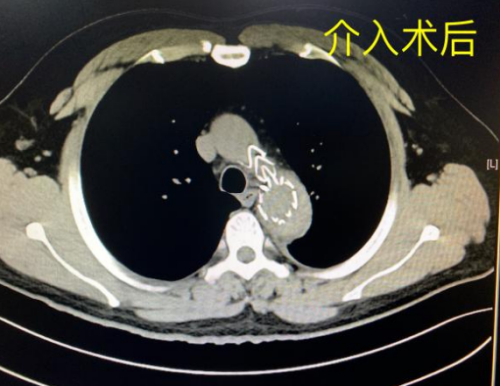

紧接着,外周血管介入科主任、主任医师赵扬程为杨淮在全麻下行主动脉覆膜支架腔内隔绝术+锁骨下动脉球囊血管成形术+腹主动脉造影+胸主动脉造影术,术程顺利,术后患者在EICU进行严密监护治疗。经过3天的精心治疗和护理,患者病情趋于稳定,成功转入普通病房,患者及其家属对医务人员感激不已。

介入术植入腹膜支架后 CT检查影像学显示